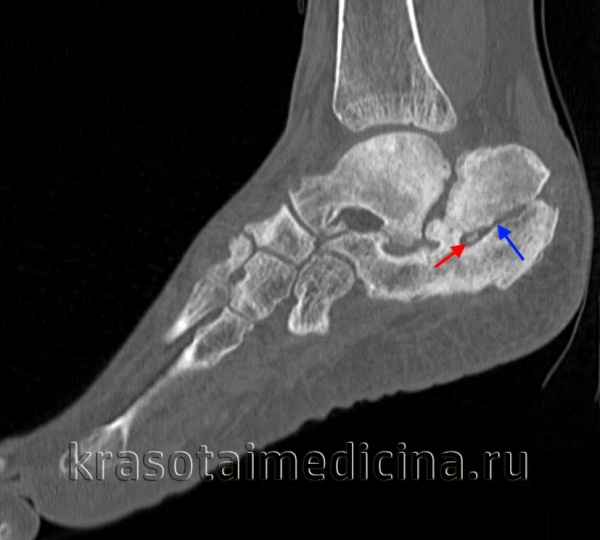

КТ стопы. Посттравматический хронический остеомиелит пяточной кости с наличием секвестра (красная стрелка) и свищевого хода (синяя стрелка).